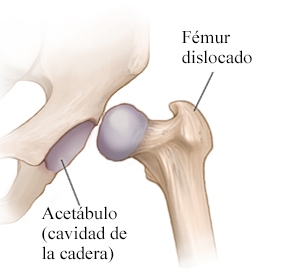

¿Qué es la displasia de cadera?

Es una laxitud o inestabilidad de la articulación que puede llegar hasta una luxación completa. Se presenta desde el nacimiento y durante los primeros meses de vida.

El ginecólogo los tranquilizó: desde 2023, el tamiz de cadera está incluido en la Cartilla Nacional de Vacunación. Detectar el problema entre la cuarta y sexta semana de vida permite un tratamiento sencillo con arnés ortopédico, evitando cirugía y desgaste prematuro.

Detectada a tiempo, la displasia se corrige con el Arnés de Pavlik, que mantiene la cadera en la posición adecuada sin causar molestias. El seguimiento debe estar a cargo de un ortopedista pediatra con entrenamiento en ultrasonido.